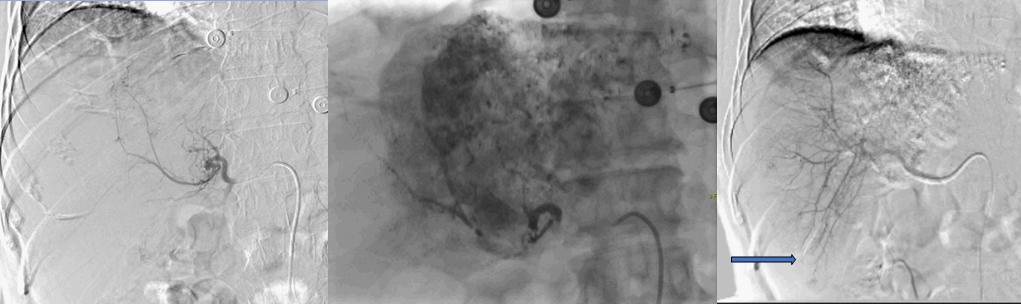

后来家属打听到有一种微创介入的方法,副作用相对较轻,可以治疗肝癌。为了寻求进一步的治疗,患者找到了唐田主任。入院后经会诊后,决定对肖先生采用介入综合治疗,也就是在影像设备的引导下,经左侧手臂肱动脉入路,将特制的导管、导丝等精密器械对体内肿瘤进行针对性的诊治。

肝左动脉供血 碘化油:20ml+THP:50mg栓塞微球(300um) 肝右叶子灶形成

介入治疗指的是临床医生在核磁、超声、X线等影像诊断的监视和引导下,将微小导管介入到患者肿瘤血管处并注入高浓度抗癌药物,能够杀死或饿死肿瘤细胞,也可以通过先进的氩氦冷冻技术冻死肿瘤细胞。